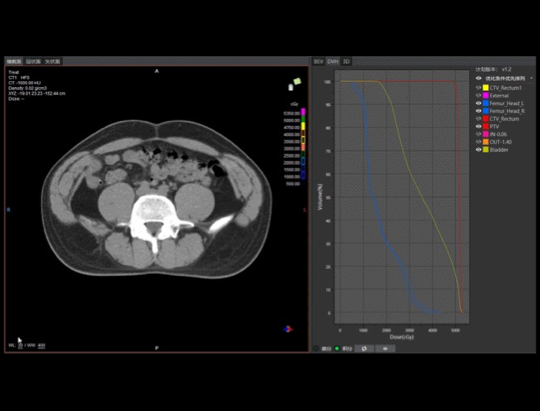

2021年3月2日早9点,这一畅想迎来了首次临床检阅:医生、物理师、技术员三方首次汇聚在控制室内,运用All-In-One一站式放疗技术为一例直肠癌患者进行首次放疗。CT模拟定位、智能勾画与审核修改、自动计划、自动复位、计划评估与审核、CT影像引导、治疗与EPID实时剂量监测质控依次在紧张有序地操作下进行,整个流程在23分钟内一气呵成,颠覆了传统至少数天才能完成的首次放疗流程。这是应用人工智能技术打造的全新肿瘤治疗模式,自此开启肿瘤诊疗智能2.0时代。